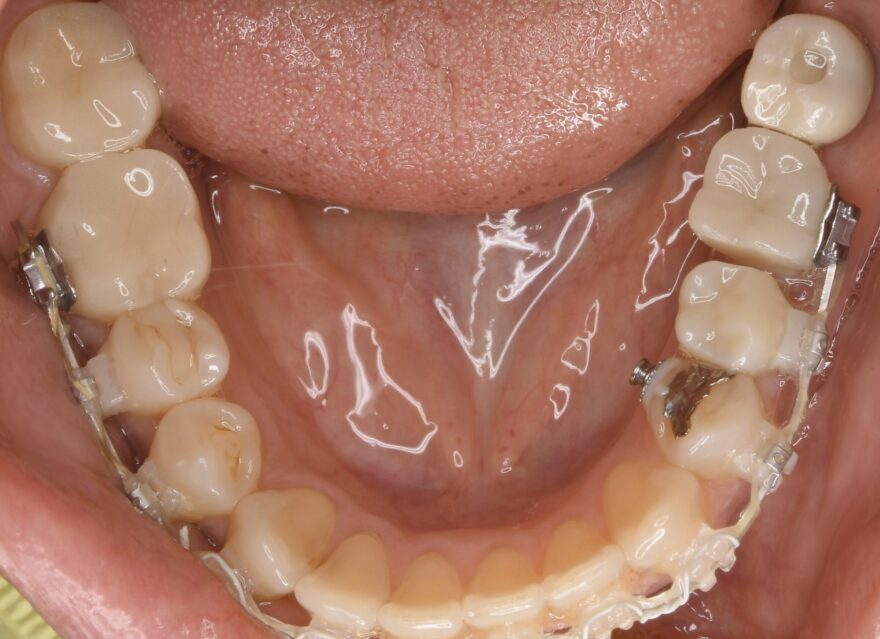

初診時の口腔内写真

左下の奥歯が崩壊しています。

治療中の口腔内写真

下顎の前歯にも、後戻り防止のためのワイヤーを装着しています。